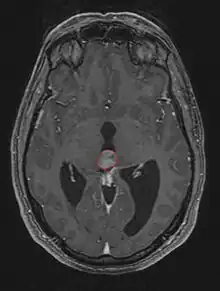

Frequently, paralysis of upward gaze along with several ocular findings such as convergence retraction nystagmus and eyelid retraction also known as Collier's sign and Light Near Dissociation (pupil accommodates but doesn't react to light) are known collectively as Parinaud's syndrome[1] or Dorsal Mid-brain syndrome, are the only physical symptoms seen. This is caused by the compression of the vertical gaze center in the midbrain tectum at the level of the superior colliculus and cranial nerve III. Work-up usually includes Neuro-imaging as seen on the right.